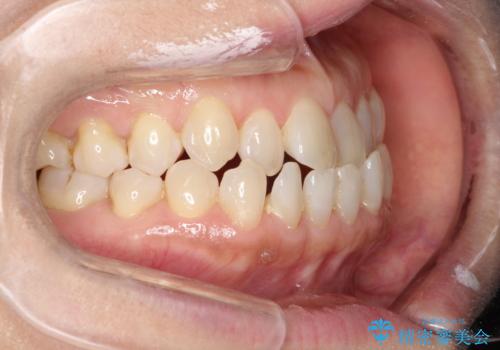

前歯の隙間 インビザラインによる目立たない成人矯正

- 前歯の隙間を気にされて来院されました。

インビザラインにて、目立たずに矯正治療を行うこととしました。

歯と歯の間にある隙間を閉じるのは、インビザラインでもしっかり治療できます。